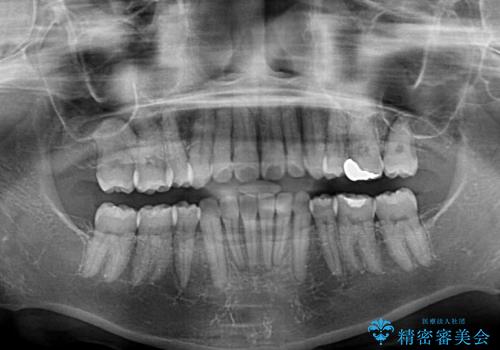

- 上下前歯の叢生を気にして来院された患者様です。

費用を抑え、期間もあまりかけずに治療をしたいとのことで、インビザライン・ライトを用いて矯正治療を行うこととしました。

インビザライン・ライトは、製作できるアライナーの枚数に制限があるため、移動可能な量に限りがあります。

一方で、半年程度で治療を終えることができるため、軽度の歯列不正の患者様には大変お勧めです。